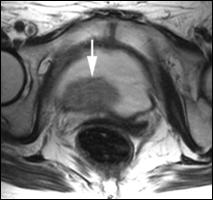

4.4. Rezonanta magnetica nucleara ofera cateva avantaje comparativ cu tomografia computerizata: tesutul tumoral este diferentiat mai bine de peretele vezical normal; examinarea se poate efectua in mai multe planuri; ganglionii limfatici se individualizeaza mai bine, putand fi deosebiti de vasele sanguine, si nu este necesara administrarea i.v. de substanta de contrast. In acelasi timp insa, miscarile pacientului pot induce artefacte neinterpretabile pe film, iar pacientii cu stimulatoare cardiace, clipuri vasculare metalice sau alte proteze metalice reprezinta contraindicatii pentru examenul prin RMN.

Cu toate progresele investigationale imagistice moderne, nici o tehnica de examen nu poate diferentia cu certitudine tumorile Ta de T1 sau T2 de T3a. Cel mai mare beneficiu diagnostic al tomografiei computerizate si al rezonantei magnetice nucleare consta in diferentierea corecta a tumorilor infiltrative, dar inca intra-organ (pana la T3a) de cele cu extensie extravezicale (T3b - T4a sau b). In privinta adenopatiei regionale, prin ambele metode se apreciaza ca ganglionii cu diametre mai mari de 1 cm sunt practic totdeauna invadati tumoral, in timp ce adenopatiile cu diametre mai mici considerate reactive, desi in cadrul acestora unele sunt totusi determinari neoplazice.

a. b.

c. d.

Figura 43. a,b,c,d) Imagini RMN de tumora vezicala.